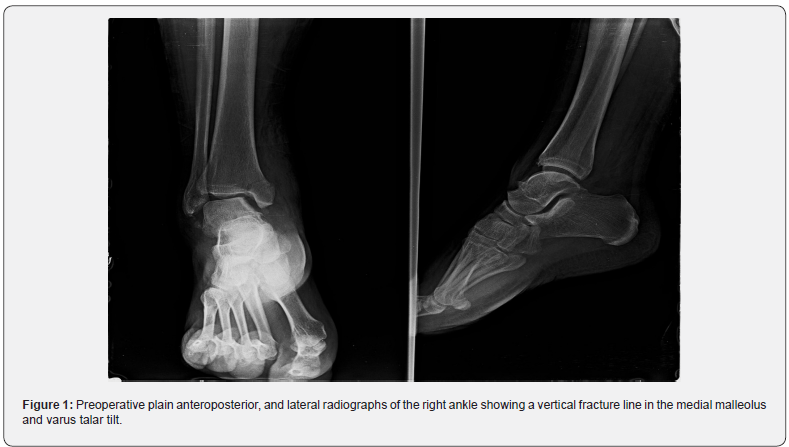

A 30-year-old male patient presented with acute-onset right ankle pain. Four years previously, he had sprained his ankle several times during practice soccer. Subsequently, the ankle pain worsened, and he had tenderness on the medial aspect of his right ankle. The symptoms were mild at rest but increased upon walking and training soccer. Plain radiographs of the right ankle showed a vertical fracture line in the medial malleolus and tilting of the talus, demonstrating the lateral instability of the ankle (Figure 1).

Rettig et al. [10] reported the first case series of stress fractures of the medial malleolus. They established 3 basic criteria for identifying medial malleolar stress fractures: tenderness over the medial malleolus and joint effusion; pain during activities before an acute episode; and a vertical line from the tibial plafond. Plain radiographs are frequently normal in the early phase because the medial malleolus consists mainly of cancellous bone. Additional imaging using CT, MRI, or nuclear bone scans is recommended [11-13]. In this case, plain radiographs of the right ankle showed a vertical fracture line in the medial malleolus and tilting of the talus, demonstrating the lateral instability of the ankle. Ankle sprain is reported to be among the most common recurrent injuries. About 20% of acute ankle sprain patients develop chronic ankle instability. The failure of functional rehabilitation after acute ankle sprain leads to the development of chronic ankle instability. Unlike acute ankle sprain, chronic ankle instability might require surgical intervention [14].

Lateral ankle sprains are a common consequence of physical activity. If not managed appropriately, a cascade of negative alterations to both the joint structure and a person’s movement patterns continue to stress the injured ligaments. These alterations result in an individual entering a continuum of disability as evidenced by the 30 % of ankle sprains that develop into chronic ankle instability (CAI) and up to 78 % of CAI cases that develop into post-traumatic ankle osteoarthritis (OA) [15]. In this case, the history of repeated ankle sprains and the 3 diagnostic criteria listed above led us to us focus on lateral instability and medial malleolar fracture. Plain radiograph showed a vertical fracture line in the medial malleolus and varus talar tilt [16].